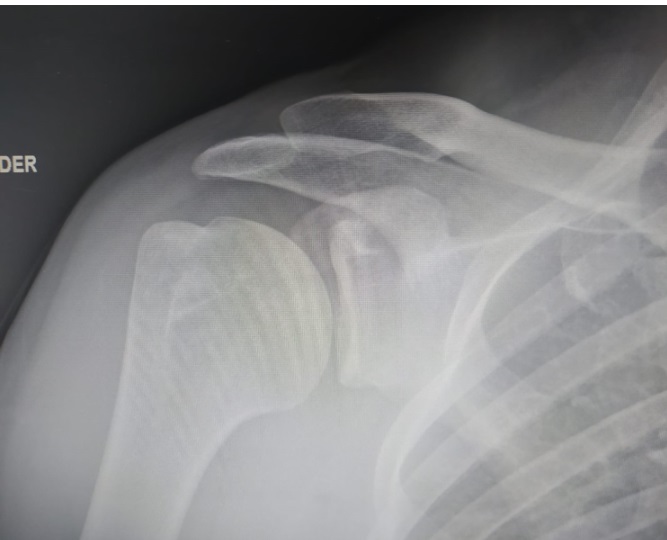

• Se realizó una radiografía de hombro, donde no se encontraron alteraciones.

• Diagnóstico diferencial: tendinitis o rotura de cualquier músculo del manguito de los rotadores (con mayor probabilidad del músculo subescapular, de acuerdo a la exploración física), calcificaciones ligamentosas del manguito de los rotadores, artritis glenohumeral o acromioclavicular, bursitis subacromial, fractura ósea.

• Juicio clínico: avulsión del tendón del músculo subescapular del hombro derecho.